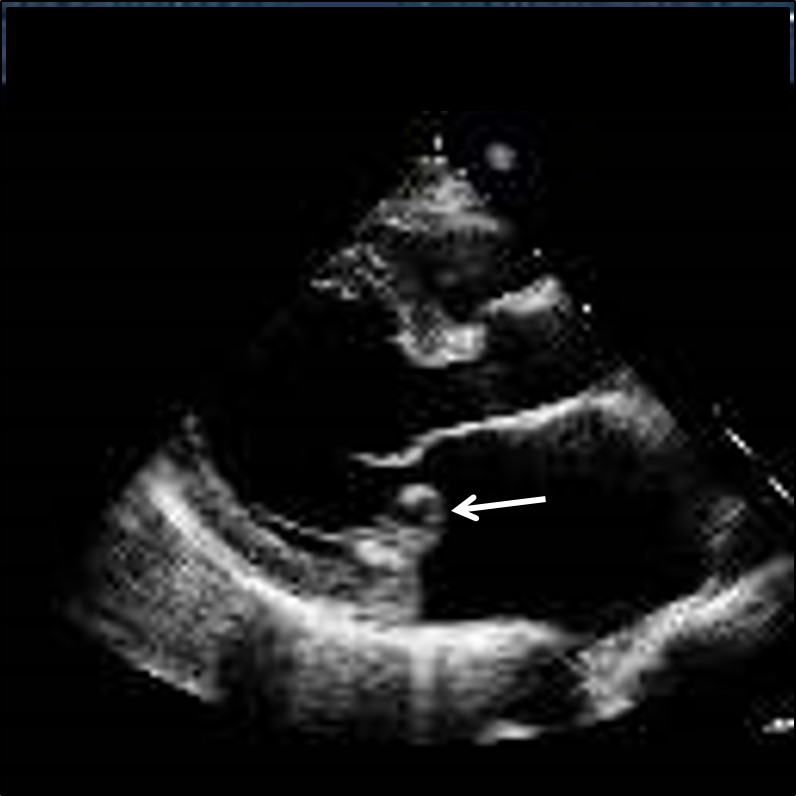

Mitral valve prolapse

• Congenitally defective (e.g. bicuspid aortic valve, mitral valve prolapse);